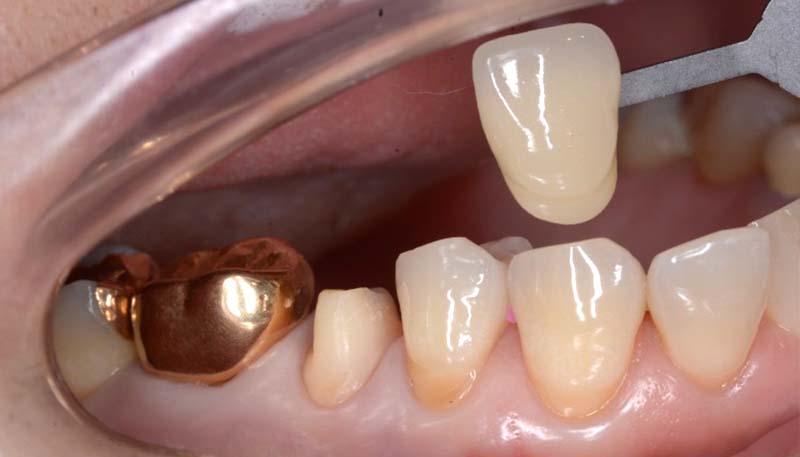

インプラントの症例 インプラントの症例

治療前〜治療後のレントゲン写真

患者様の要望過去に治療したブリッジを外し咬み合わせの平面を整えて、被せ物や詰め物を綺麗にしたい。

治療期間10ヶ月

治療費用約1,600,000円

治療内容インプラント2本、アンカースクリューを用いた部分矯正、

セラミックによる補綴治療

治療のリスクセラミックの破折の

可能性